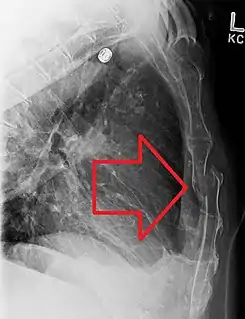

Una fractura esternal desplazada

En el diagnóstico se pueden utilizar las manifestaciones clínicas de una fractura, que incluyen: dolor, tumefacción, deformación, equimosis, inestabilidad y crepitación. Para confirmar el diagnóstico, se utilizan dos radiografías en distintos ángulos y TAC ( tomografía axial computarizada ).[5]